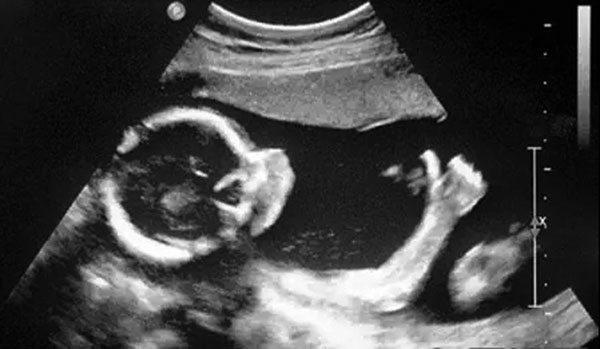

B超像挑西瓜前敲一敲

B超的原理是用超声波穿透人体,当声波遇到人体组织时会产生反射波,通过计算反射波成像。就像挑西瓜一样,边敲边看显示病灶情况。

4、腹部盆腔——除肠道外,一般超声都能检查

腹腔器官受呼吸影响较大,进而影响到CT、核磁成像,而超声不会因此受影响。同时,超声对肝脏、脾脏、胰腺、肾脏、盆腔等器官诊断准确率较高。

但是超声受气体干扰很大,对于肠道等含气较多的器官,超声诊断准确率会降低。